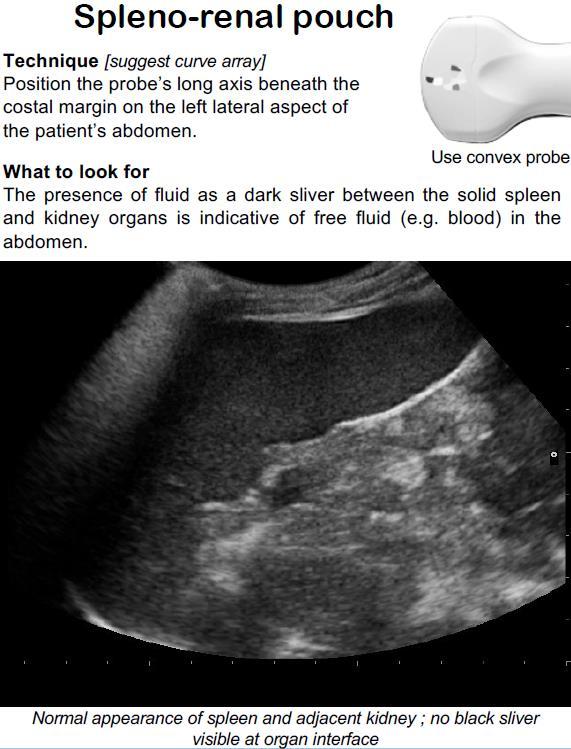

Ultrasound